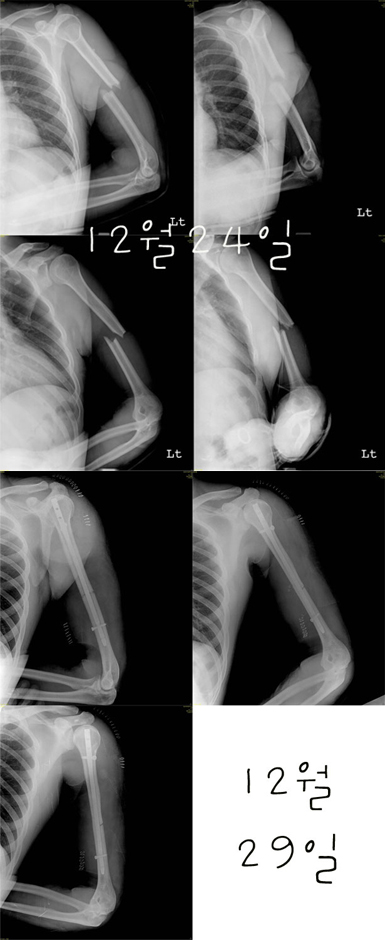

크리스마스 선물로 큰걸 받으셨군요...

전 우측 상완골 골절................그래도 깔끔하게 부러지셨네요.

저도 2008년 3/1에 부러져서 저렇게 철판과 피스8개가 아직도 박혀 있는데...

왼쪽상완골.킥에서.ㅎ

저랑 완전 똑같이 뿌러지셨네요.똑같은수술.ㅎ

저랑똑같네요ㅋㅋ 저는 1월 18일날 하이원 레인보우에서 ㅋㅋ

전치 6주,, 수술자국보면 아직도 짜증 ㅠ,ㅠ